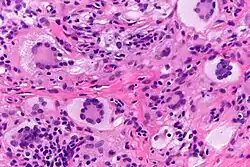

Histopathology of juvenile xanthogranuloma characteristiclaly shows scattered Touton giant cells.[6]